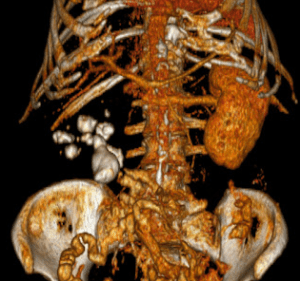

TOMOGRAFIA AXIAL COMPUTARIZADA SIN CONTRASTE

Actualmente se considera la prueba de elección dado su alto rendimiento diagnóstico. Permite una valoración más rápida de la vía urinaria y de la litiasis. Las determinación de las unidades de Hounsfield permite determinar la composición de la litiasis. Permite además la reconstrucción espacial de la vía urinaria mediante sofware especializado.